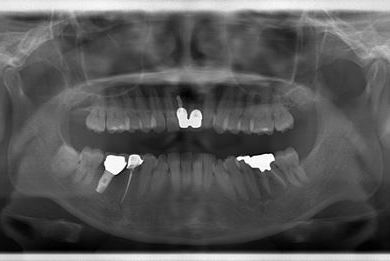

インプラント治療+セラミック治療

| 性別/年齢 | 女性 / 42歳 | ||||||||||||||||||||||||||||||||

| 主訴 | 別の病院で、右奥歯の根の部分にインプラント治療が必要と言われたので、セカンドオピニオンを希望。 | ||||||||||||||||||||||||||||||||

| 治療方針 | 右下奥、保存不能の歯を抜歯し、インプラント治療にて、機能的・審美的回復を行う。 | ||||||||||||||||||||||||||||||||

| 治療内容 | インプラント1本、メタルボンドセラミッククラウン2本(メタルボンド用土台1本) | ||||||||||||||||||||||||||||||||

| 総治療費 | 502,740円 | ||||||||||||||||||||||||||||||||

| 治療期間 | 1年3ヶ月 |